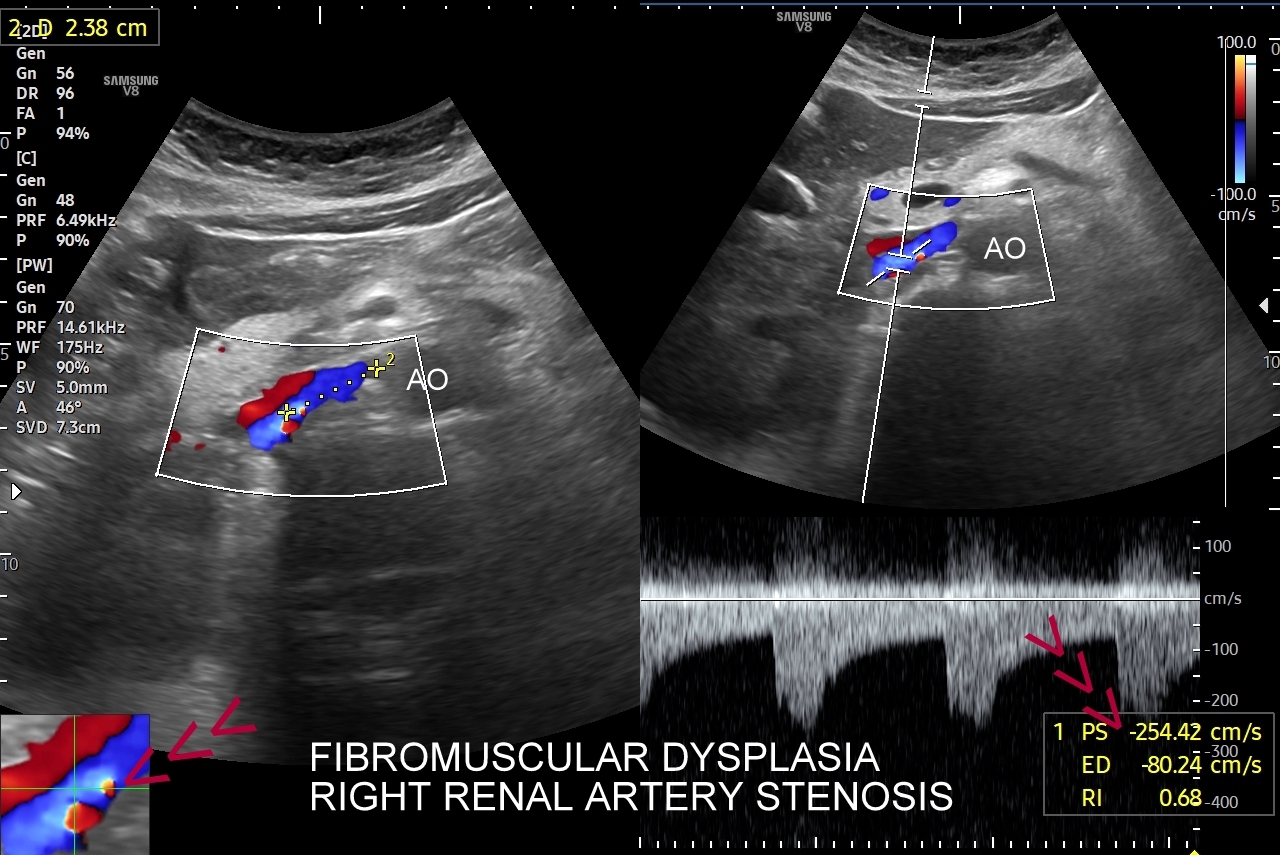

Doppler przepływów nerkowych (USG przepływy nerkowe) jest połączeniem badania obrazowego USG z badaniem funkcjonalnym nerki, jej naczyń tętniczych i żylnych oraz globalnie stanu układu krążenia. Najczęstszym wskazaniem do wykonania USG Doppler tętnic nerkowych, będącego częścią USG Doppler przepływów nerkowych, jest nadciśnienie tętnicze i poszukiwanie jego przyczyn w postaci zwężenia tętnic nerkowych, które mogą wystąpić w odcinku przednerkowym, jak i wewnątrznerkowym. Wykonanie oceny dopplerowskiej nerki jest szczególnie ważne w przypadku wystąpienia nadciśnienia tętniczego u osób młodych lub u dzieci.

Inne wskazania do przeprowadzenia diagnostyki USG przepływów nerkowych obejmują ocenę funkcji nerek w przebiegu chorób ostrych oraz przewlekłych, takich jak nefropatia cukrzycowa, glomerulopatie, czy zapalenia kłębuszków nerkowych. Badanie USG Doppler wykonywane jest również przy podejrzeniu zakrzepicy żyły nerkowej i zespołu „dziadka do orzechów”; przy stwierdzeniu obecności żylaków powrózka nasiennego u mężczyzn; żylaków miednicy u kobiet; w sytuacjach, gdy podczas standardowego badania USG jamy brzusznej uwidoczniono patologię nerki (np. guz nerki, marskość); a także przy stwierdzeniu podwyższonych wartości parametrów nerkowych w badaniach laboratoryjnych (kreatynina, mocznik, cystatyna C, potas) oraz w ramach oceny USG nerki przeszczepionej.